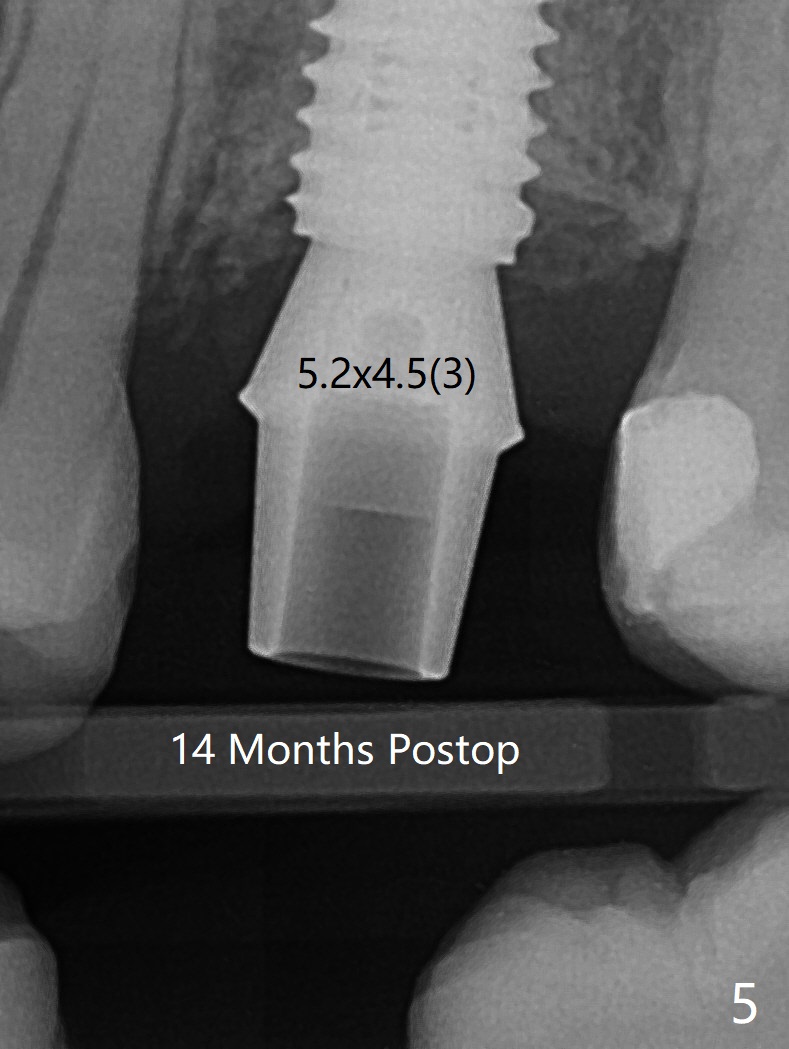

When a 4.5x10 mm implant is placed with sinus lift at #14 (Fig.1), a 5.2x8(2) mm temporary abutment is inserted with height adjustment. Advantage is that an immediate provisional (Fig.2 yellow lines; Fig.3 P) has an ideal emergency profile so that there is less chance of food impaction associated with the future permanent crown. It appears that the mesial portion of bone graft in the mesial gap has been converted to the native bone (lamellar) in 3 months (Fig.4). Bone graft appears to be integrated to the native bone and the implant 14 months postop (Fig.5).